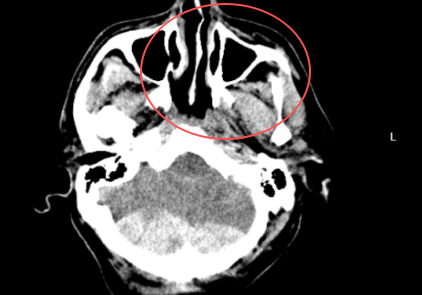

近日,紹興袍江醫(yī)院急診科緊急接收了一名由120轉(zhuǎn)運來的意識不清危重患者。經(jīng)快速檢查,患者被確診為創(chuàng)傷性枕部跨竇硬膜外血腫、創(chuàng)傷性蛛網(wǎng)膜下腔出血、左側(cè)額顳部硬膜下血腫,同時合并全身多處損傷,病情危急。罕見“對沖傷”疊加小腦創(chuàng)傷,病情半小時內(nèi)急轉(zhuǎn)直下該患者所受損傷為顱腦“對沖傷”,即頭部前后方同時受力受損,是多發(fā)傷中的常見類型。更棘手的是,患者合并小腦創(chuàng)傷——這一創(chuàng)傷類型在所有顱腦創(chuàng)傷中占比僅2%-5%,臨床處理難度極大。圖片有可能引起不適,慎點患者入院后病情迅速惡化,半小時內(nèi)即2025-10-07